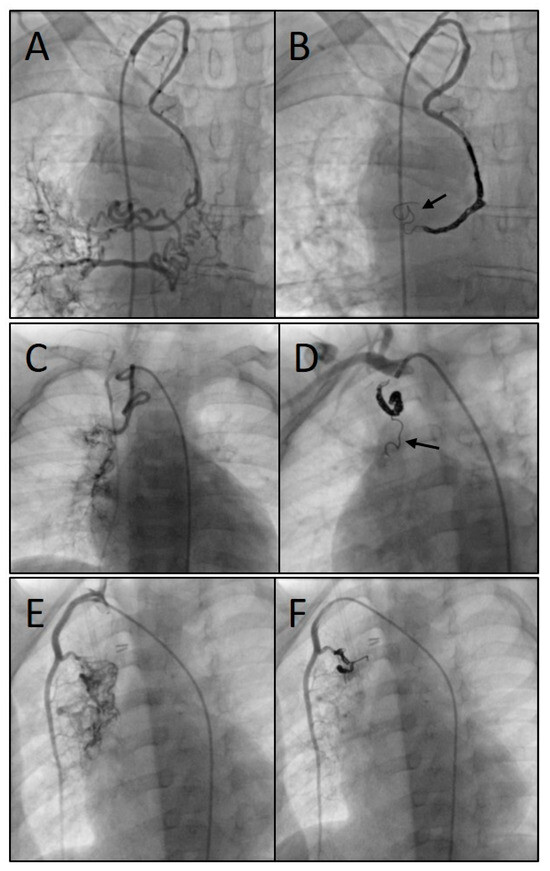

2.2. Catheterization and Transcatheter Embolization